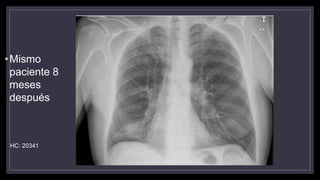

•Mismo

paciente 8

meses

después

HC: 20341

•Mismo paciente 8 meses después. Masa LID